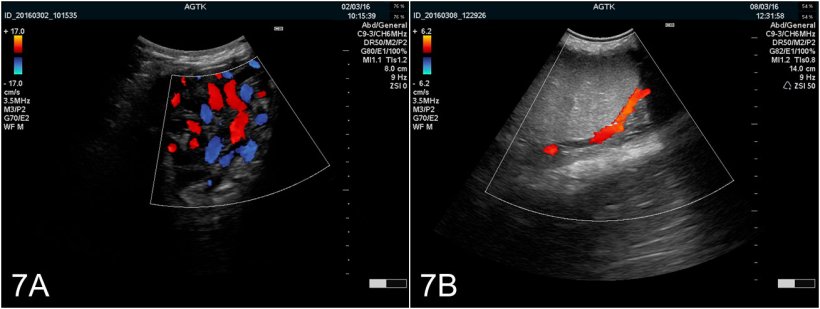

Riassumento, l'ecografia del tratto riproduttivo del verro è una tecnica diagnostica possibile che può portare informazioni di valore rispetto alla funzionalità e salute del tessuto. Nonostante l'uso in pratica sia molto limitato, l'autore è fermamente convinto che l'uso della tecnica (oltre altre come il Doopler a colore [figura 7A e B]) tendono ad essere più utilizzati tra i veterinari di suini come strumento per la stima delle future performance degli eiaculati e per diagnosticare in modo preciso problemi di subfertilità ed infertilità associati a tessuti malati.

Figura 7:Imágenes del testículo obtenidas mediante ultrasonografía Doppler color. A) Vasos del cordón espermático. B) Arteria testicularis